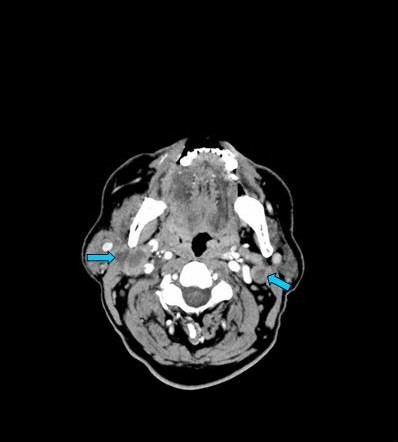

En la imagen radiológica se observan adenopatías bilaterales derechas en área II-III de 16 mm, observándose otras similares adyacentes. Se le realiza biopsia diagnosticando un carcinoma epidermoide de orofaringe.

DIAGNOSTICO FINAL: CARCINOMA DE OROFARINGE